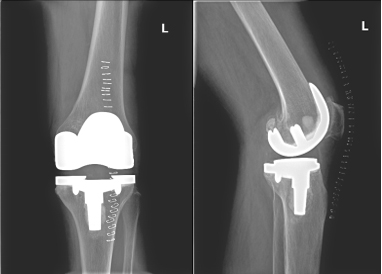

此病情困扰邱阿婆多年,严重影响日常生活,在我院住院期间,严格评估手术风险,精心准备手术,行左膝人工关节置换术,术后中西医结合诊治以及科学功能锻炼,术后1周可自行下地活动,术后2周可自行上下楼梯,术后1月可自行去市场买菜,日常生活基本可以自理。

术后X片:

膝关节置换术是中治疗严重膝关节功能障碍的新技术,可以非常有效的根除晚期膝关节疼痛,纠正关节畸形,极大的提高病人的生活治疗,主要是针对严重的膝关节疼痛、不稳、畸形、日常生活活动严重障碍,经过保守治疗无效或效果不明显的老年患者,如类风湿关节炎、骨性关节炎、创伤性关节炎等引起的严重关节功能障碍,我院骨伤科通过中西医结合诊疗,手术以及术后康复相结合,动静结合、筋骨并重的诊疗思维,通过精细的手术以及科学的康复训练方法,可有效的减少手术并发症以及更快、更有效的恢复关节功能,最大限度的改善患者生活质量。